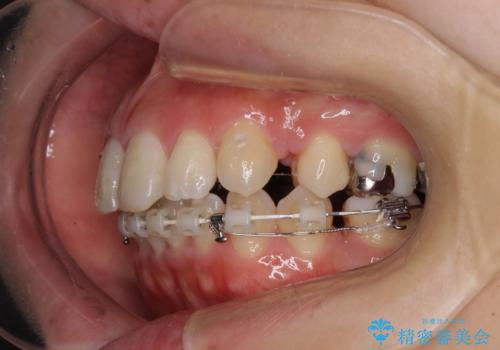

突出した口元が気になる ハーフリンガル装置による抜歯矯正

- ハーフリンガル

- 口元の突出感を気にして来院された患者様です。

通常では上下左右の第一小臼歯4本を抜歯しますが、下顎が左側にシフトしていたため、下顎左側のみ第二小臼歯を抜歯し、正中を合わせながら口元を下げる治療計画としました。

ハーフリンガルは、通常では表側のワイヤー矯正よりも治療期間がかかります。特に今回のように下顎左側をイレギュラーの第二小臼歯抜歯としたため、さらに時間がかかることが予想されました。

実際に治療をおこなってみると、2年を切る短期間で治療を終えることができました。